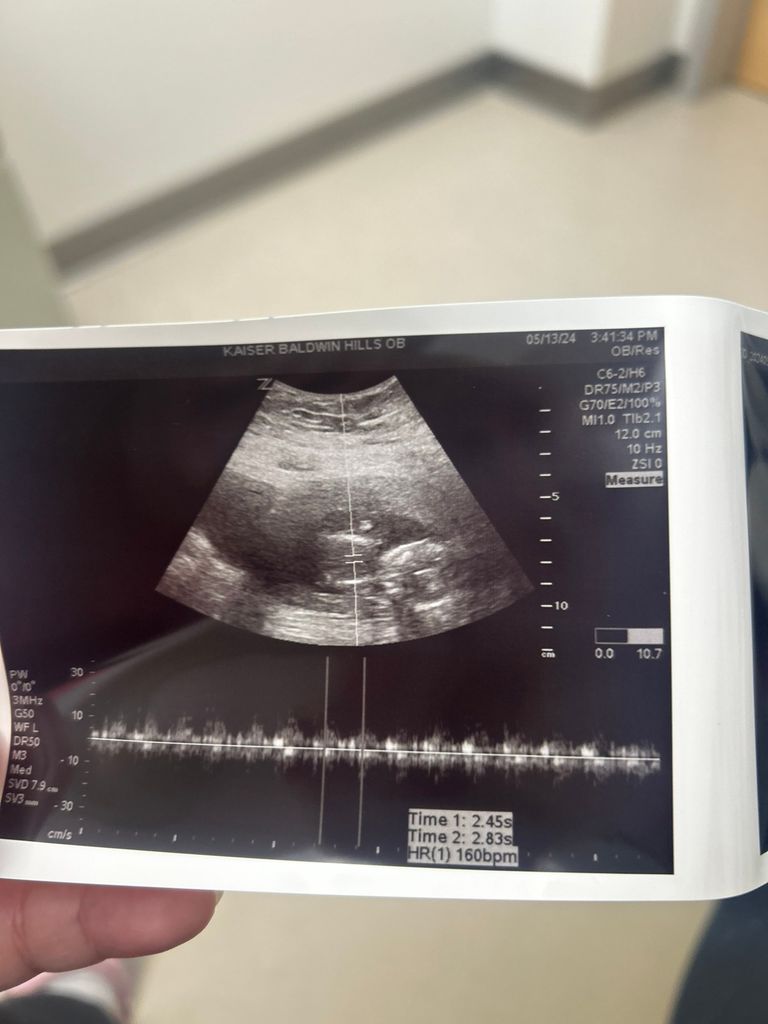

Is my baby too small? November 2024 Babies Forums What to Expect Is My Baby Too Small No, there's not necessarily anything wrong if your baby is small for dates. The most common definition of fetal growth restriction is a fetal weight that is below the 10th percentile for gestational age as determined through an ultrasound. Babies grow at different rates and some are. Are there different types of fetal growth restriction? Fetal growth restriction (fgr), formerly. Is My Baby Too Small.